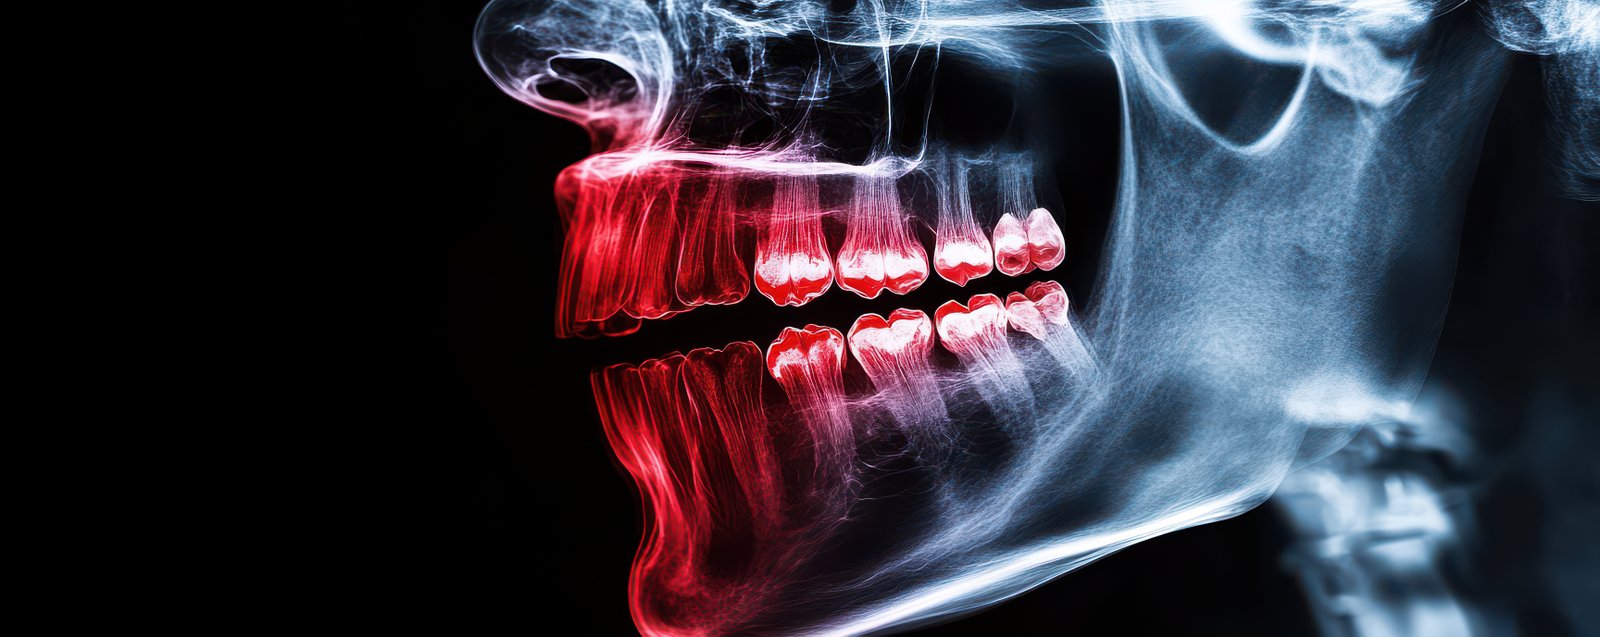

Dental trauma requires immediate attention and expert care to prevent long-term complications. At Dr. Mahajan’s Toothville, we provide prompt and precise management of injuries affecting the teeth, jaws, and surrounding facial structures. Our trauma care includes treatment for broken or fractured teeth, knocked-out teeth (avulsions), soft tissue injuries, facial swelling, jaw fractures, and sports-related dental injuries. Using advanced diagnostic imaging and clinical evaluation, we accurately assess the severity of the injury and create an effective treatment plan tailored to each patient.